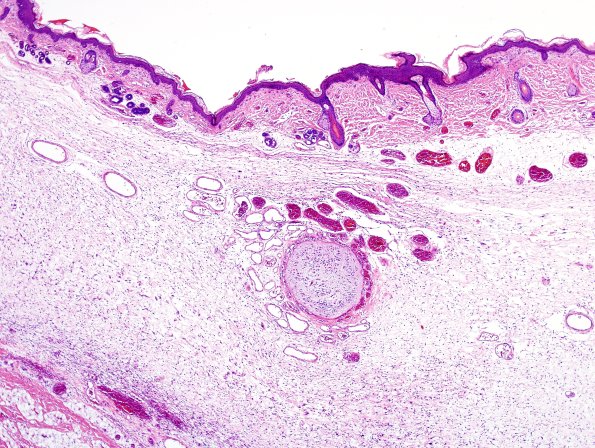

Washington University Experience | DEVELOPMENTAL MALFORMATIONS | Encephalocele | 7A2 Encephalocele (Case 7) H&E 1A

Sections of both the "inferior" and "superior" occipital lesions show hair bearing skin with foci of ectopic neural tissue with an associated complex vascular network particularly evident. (H&E)